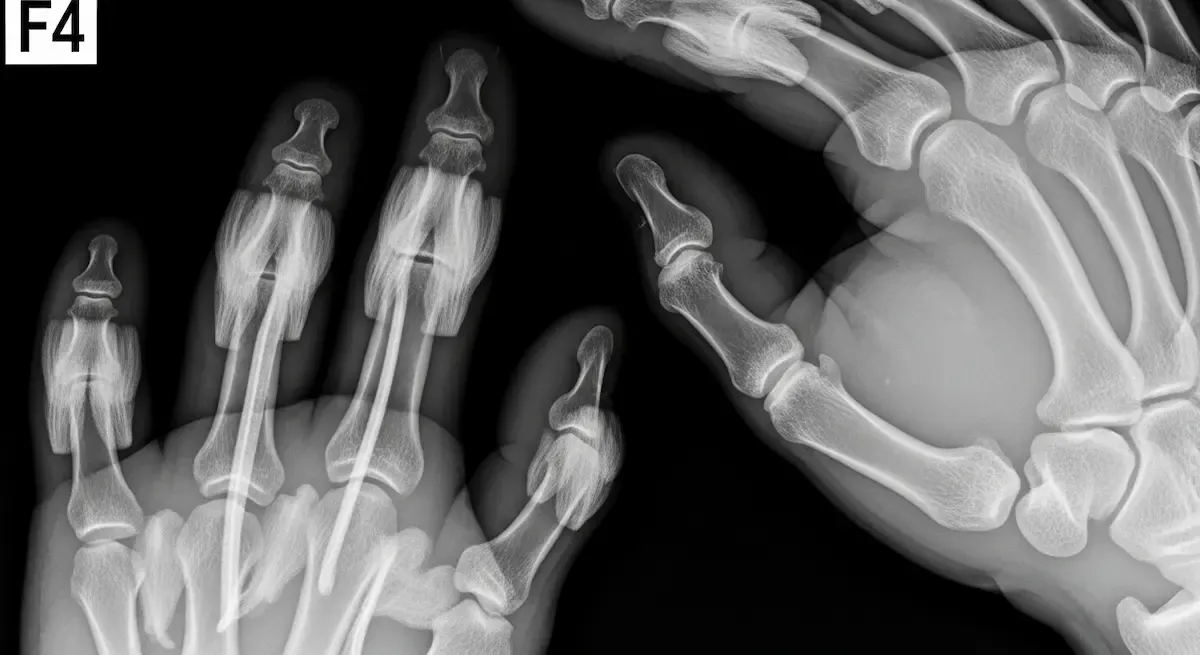

Ao longo da minha trajetória como ortopedista especializado em cirurgia da mão e punho, a bossa carpal é uma das condições mais frequentes que encontro em meu consultório. Esta protuberância no dorso do punho, tecnicamente conhecida como cisto...